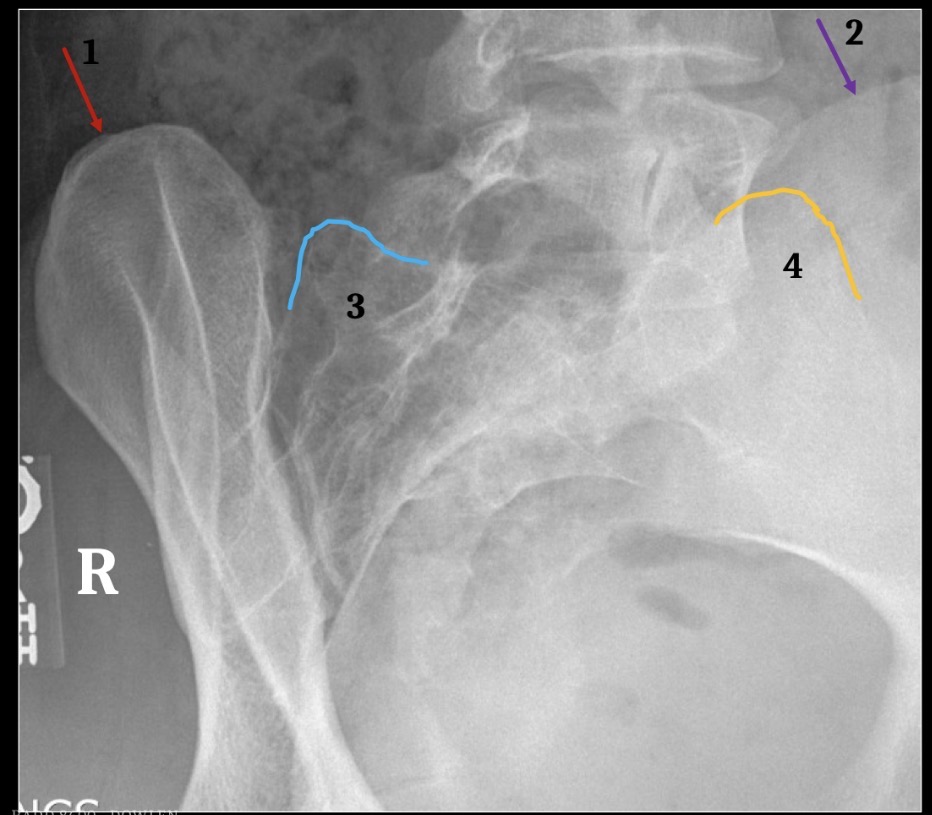

1

Inferior Margin of right 1th rib

2

Spinous process of T12

3

Left pedicle of L2

4

Left transverse process of L3